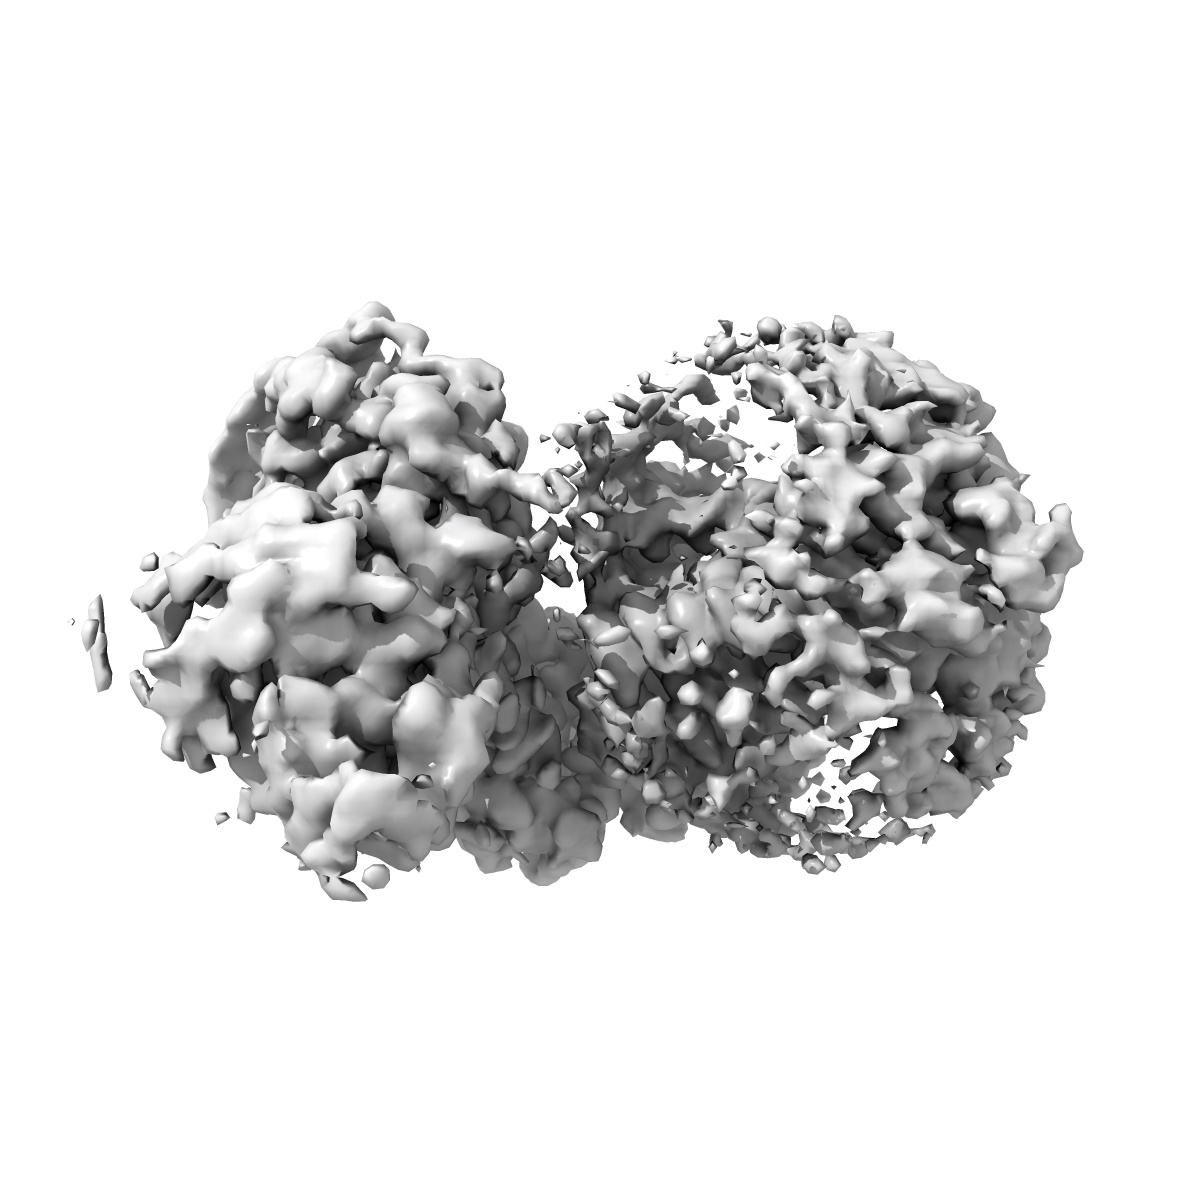

Structural basis of D9-THC analog activity at the Cannabinoid 1 receptor

Sample: HU210/CB1/Gi1 signaling complex

Structural basis of Delta 9 -THC analog activity at the Cannabinoid 1 receptor.